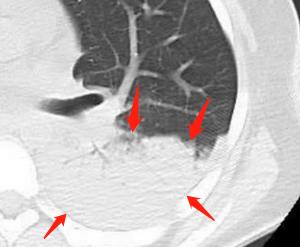

1.“树芽征”和小叶中心结节:

结核引起小气道炎症,形态类似小树芽

小树芽